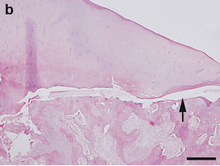

Hematoxylin and eosin staining. Bar = 200 μm.

OCD also is found in animals, and is of particular concern in horses, as there may be a hereditary component in some horse breeds.[94] Feeding for forced growth and selective breeding for increased size are also factors. OCD has also been studied in other animals—mainly dogs, especially the German Shepherd[95]—where it is a common primary cause of elbow dysplasia in medium-large breeds.[96]